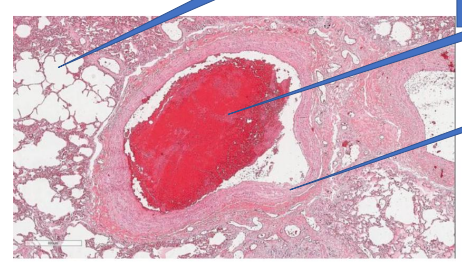

Pulmonary throbuboemboli

1- normal alveoli

2- thrombus emboli

3- vessel wall